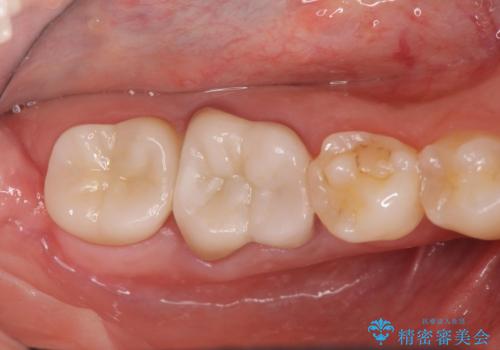

スペース狭小な銀歯を白くしたい 歯冠長延長術を併用したセラミック治療

なんとかギリギリのスペースを確保するこおtができ、無事銀歯を外してセラミック治療を行うことができました。